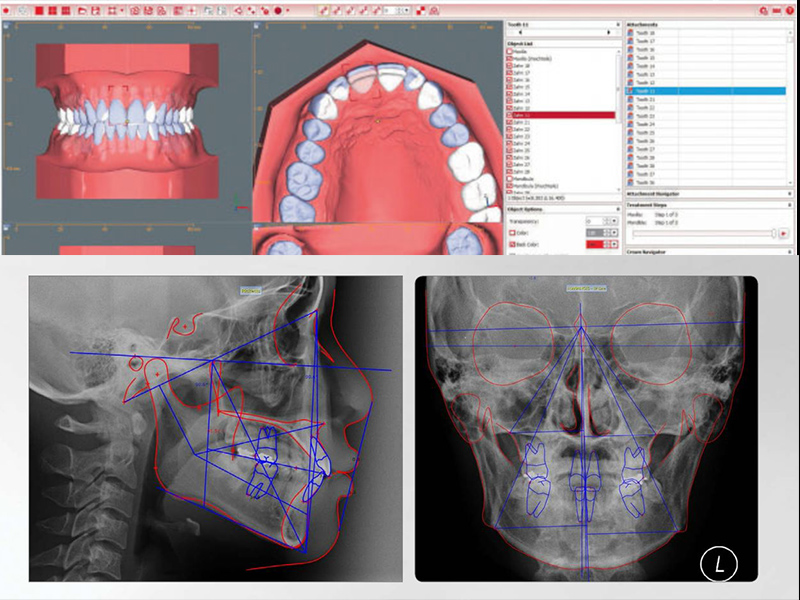

투명교정은 정교함이 핵심 POINT! 수치과병원은 “치과용 고정밀 3D프린터, 3D스캐너”를 사용하여 치아를 정밀 스캔하여 정확도와 예측성을 높입니다.